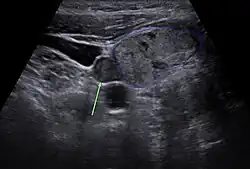

Vor einer geplanten Operation können Lokalisation und Größe der betroffenen Nebenschilddrüsenkörperchen durch Sonografie, Szintigrafie mit Technetium-99m-Sestamibi (Nebenschilddrüsenszintigrafie), Computertomographie oder Kernspintomografie dargestellt werden.

Ultraschallbild einer Schilddrüse vom Hund mit Adenom der Nebenschilddrüse

Die Sensitivität dieser diagnostischen Verfahren ist jedoch begrenzt. Besonders bei komplizierteren Fällen, wie zum Beispiel bei Vorhandensein von mehreren auffälligen Nebenschilddrüsen oder entfernt auftretenden Nebenschilddrüsenadenomen, kann eine zuverlässige Lokalisation aller betroffenen Epithelkörperchen schwierig sein.[60] Neuere bildgebende Verfahren, wie Positronenemissionstomographie (PET) mit speziellen Radiopharmaka wie 68Ga-Trivehexin, können in solchen Fällen eine zuverlässigere Lokalisation ermöglichen,[61] wodurch deren komplette chirurgische Entfernung und damit eine vollständige Heilung des primären Hyperparathyreoidismus wahrscheinlicher wird.